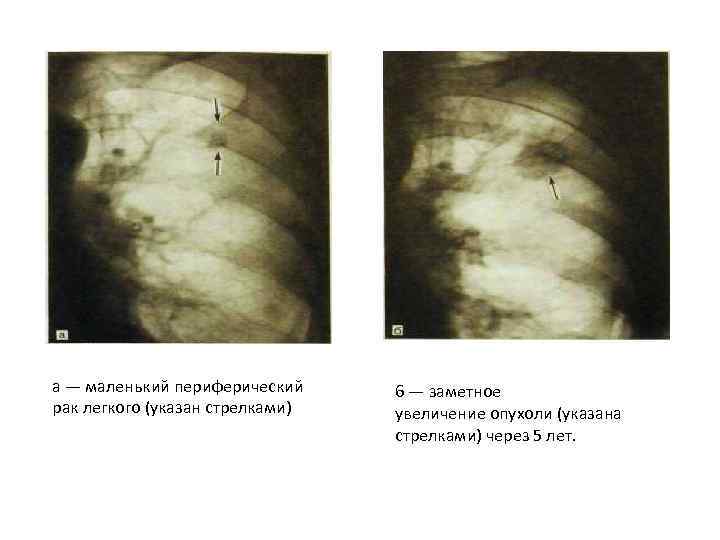

Рак легкого периферический Развивается в стенках Бронхов IV — VI порядка и более мелких ветвей. В основном располагается в верхних долях преимущественно справа, чаще у междолевых щелей в краевых участках III сегмента. Долгое время клинически может не проявляться. В начале своего развития при рентгенологическом исследовании проявляется в виде отграниченного участка деформации легочного рисунка, пневмониеподобного фокуса и реже — в виде тонкостенной полости. При размере до 1 — 2 см в диаметре периферический рак дает картину полигональной тени с неодинаковыми по протяженности сторонами, несколько напоминая звездчатый рубец. Контуры тени обычно нечеткие. Развивается опухоль чаще на фоне измененной легочной ткани. Врастая в нее, опухолевый узел образует злокачественную корону, или лучистый венчик, представляющий собой короткие (до 2 — 3 мм) линейные асимметричные тени. Эта лучистость имеет неодинаковую выраженность и не всегда выявляется по всему периметру опухоли. Интенсивность тени зависит от размеров опухолевого узла. Маленькие раки дают тень малой интенсивности. Структура тени чаще неоднородная, что обусловливается многоузловатостью опухоли, распадом се и формированием полостей.

Рак легкого периферический Развивается в стенках Бронхов IV — VI порядка и более мелких ветвей. В основном располагается в верхних долях преимущественно справа, чаще у междолевых щелей в краевых участках III сегмента. Долгое время клинически может не проявляться. В начале своего развития при рентгенологическом исследовании проявляется в виде отграниченного участка деформации легочного рисунка, пневмониеподобного фокуса и реже — в виде тонкостенной полости. При размере до 1 — 2 см в диаметре периферический рак дает картину полигональной тени с неодинаковыми по протяженности сторонами, несколько напоминая звездчатый рубец. Контуры тени обычно нечеткие. Развивается опухоль чаще на фоне измененной легочной ткани. Врастая в нее, опухолевый узел образует злокачественную корону, или лучистый венчик, представляющий собой короткие (до 2 — 3 мм) линейные асимметричные тени. Эта лучистость имеет неодинаковую выраженность и не всегда выявляется по всему периметру опухоли. Интенсивность тени зависит от размеров опухолевого узла. Маленькие раки дают тень малой интенсивности. Структура тени чаще неоднородная, что обусловливается многоузловатостью опухоли, распадом се и формированием полостей.

По мере роста опухоль приобретает шаровидную или неправильно округлую форму с неровными, бутристыми, поли-циклическими контурами. Размер опухоли в среднем 4 — б см в диаметре, но может достигать 10 см и более. Легочный рисунок в окружности опухоли изменен, количество линейных теней увеличено, образуется грубая сетка, которая может прослеживаться до периферии. В ряде случаев выявляется дорожка к корню легкого, обусловленная либо лимфангоитом, либо перибронхиальным и периваскулярным ростом опухоли. Большими диагностическими возможностями обладает томография, которая позволяет изучить структуру и контуры опухоли, бронхи и легочную ткань в ее окружности. Диагностике помогают также направленные бронхо- и ангиография. Достоверная диагностика основывается на данных, полученных во время трансторакальной пункции.

По мере роста опухоль приобретает шаровидную или неправильно округлую форму с неровными, бутристыми, поли-циклическими контурами. Размер опухоли в среднем 4 — б см в диаметре, но может достигать 10 см и более. Легочный рисунок в окружности опухоли изменен, количество линейных теней увеличено, образуется грубая сетка, которая может прослеживаться до периферии. В ряде случаев выявляется дорожка к корню легкого, обусловленная либо лимфангоитом, либо перибронхиальным и периваскулярным ростом опухоли. Большими диагностическими возможностями обладает томография, которая позволяет изучить структуру и контуры опухоли, бронхи и легочную ткань в ее окружности. Диагностике помогают также направленные бронхо- и ангиография. Достоверная диагностика основывается на данных, полученных во время трансторакальной пункции.

а — маленький периферический рак легкого (указан стрелками) 6 — заметное увеличение опухоли (указана стрелками) через 5 лет.

а — маленький периферический рак легкого (указан стрелками) 6 — заметное увеличение опухоли (указана стрелками) через 5 лет.